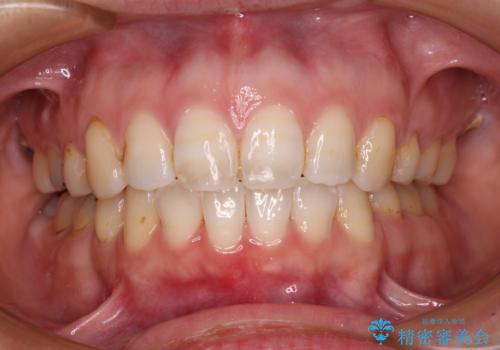

- 前歯のデコボコと隙間を気にして来院された高校生の患者様です。

下顎前歯が上顎前歯を突き上げるような咬み合わせとなっており、その影響で上顎正中に隙間ができている状態でした。

叢生の程度は軽度であり、本人もしっかりと使用する自信があるとのことだったので、インビザラインによる矯正治療を行うこととしました。